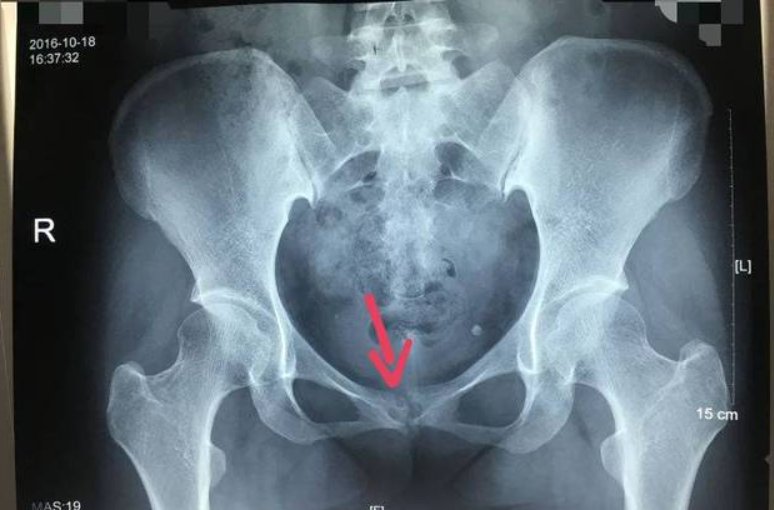

Conclusions It is an ideal way to treat pubic symphysis separation with reconstruction plate fixation.

结论重建钢板内固定治疗耻骨联合分离是一种较理想的方法.